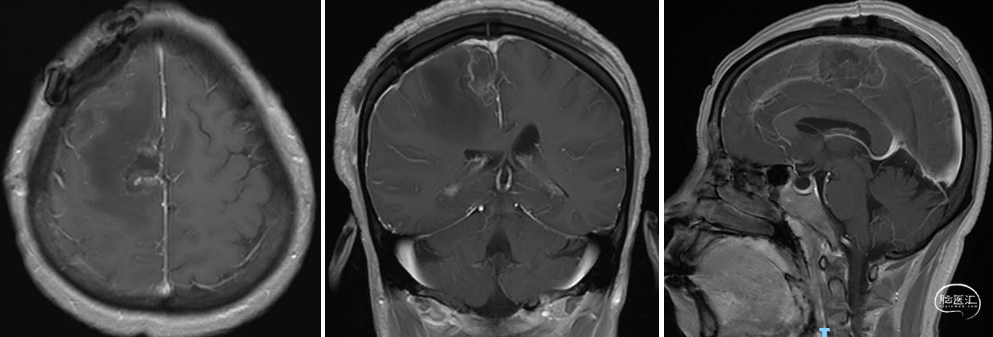

术后影像